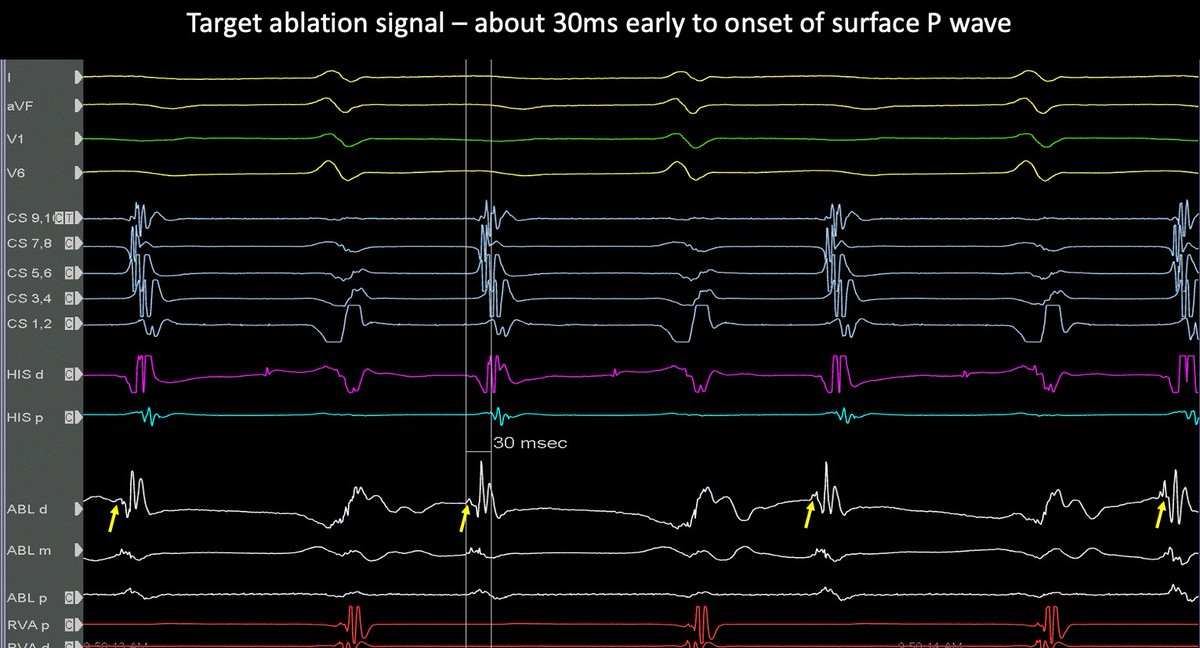

7/ Slow pathway targeted for ablation. 6s of RF was enough to totally remove the two for one responses (TFORs). Post ablation everything normalised. I thought this was a rare but satisfying case. @finnakerstrom

6/ EP study showed helped confirm. There was no VA conduction. Antegrade conduction showed continuous double fire responses without tachycardia. Very hard to systematically do an EP study.